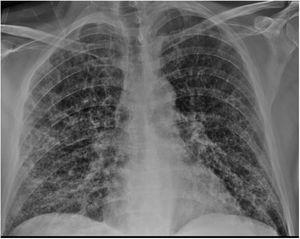

Caso clínicoVarón de 51 años que acudió a urgencias por cuadro de fiebre (>38°C) y disnea de una semana de evolución. El paciente presentaba antecedentes de EPOC, cirrosis hepática de origen no filiado y adenocarcinoma de recto (pT4N1M0). En el examen físico destacaba la presencia de hipoventilación generalizada con crepitantes finos bibasales. En la radiografía de tórax (fig. 1) se objetivaron infiltrados bilaterales con patrón en vidrio deslustrado. La analítica de sangre mostraba los valores descritos en la tabla 1. Los cultivos de sangre y orina fueron negativos. Se realizó detección de virus SARS-CoV-2 por reacción en cadena de polimerasa en exudado faríngeo, que fue positiva.